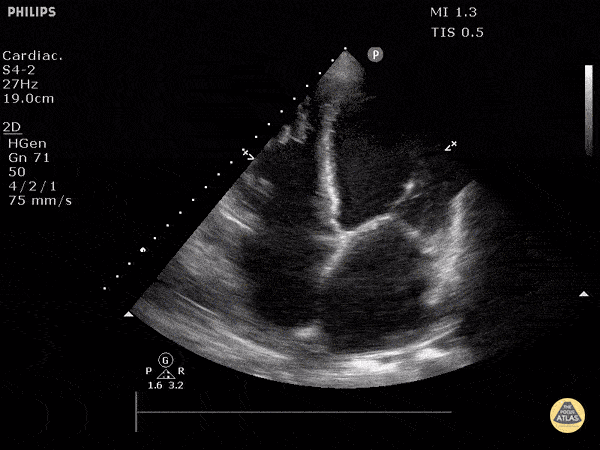

lv-versagen-apikal